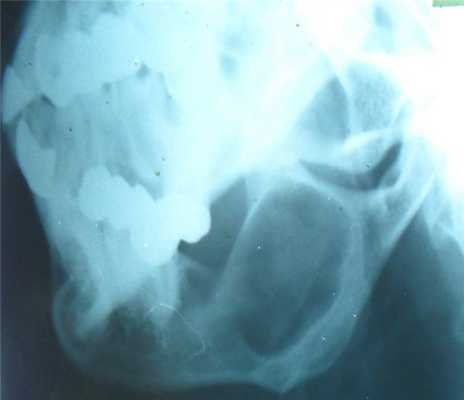

Адамантинома

- одонтогенное (зубное) эктодермальное происхождение, т.е. развивается из эмалевого органа и имеет типичное гистологическое строение,

- возникает в нижней челюсти, верхней челюсти, также в большеберцовой и локтевой костях,

- возникает в любом возрасте, но чаще у молодых людей (от 15 до 35 лет),

- очаг рассасывания костного вещества, растущий из глубины центральных участков нижней челюсти, корковый слой вздувается изнутри кнаружи и часто истончается,

- вначале дефект однородный, затем появляется крупная или мелкая ячеистость (за счет кистовидного перерождения опухолевой ткани).